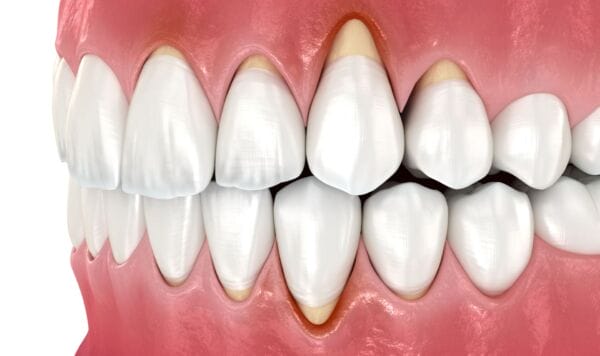

Gum disease, or periodontal disease, is a common but serious condition that affects the soft tissues and bone supporting your teeth. It typically starts with gingivitis; swollen, red, or bleeding gums caused by the buildup of plaque and tartar. If untreated, it can progress into periodontitis, leading to gum recession, bone loss, and even tooth loss.

Periodontitis is the advanced form of gum disease. It develops when inflammation from untreated gingivitis spreads below the gumline, destroying the connective tissue and bone that anchor your teeth. Symptoms can include:

Gum recession